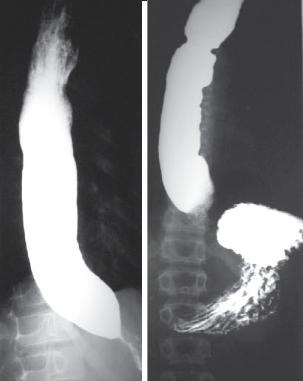

Image TOGD d'une megaoesophage sur

le cliche de face et OAD . Bord lisse et

aperistaltisme ., la retressisement a inferieure est

image en queue de radis |

Megaoesophage en face

et en profile OAD |